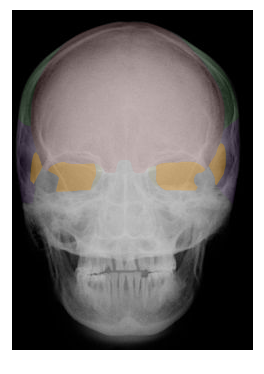

Cranial and Facial Bones

Students will use images and descriptions to reinforce their knowledge of the cranial and facial bones.

A | B |

| FRONTAL |

| SPHENOID |

in yellow,  | ETHMOID |

in green,  | PARIETAL |